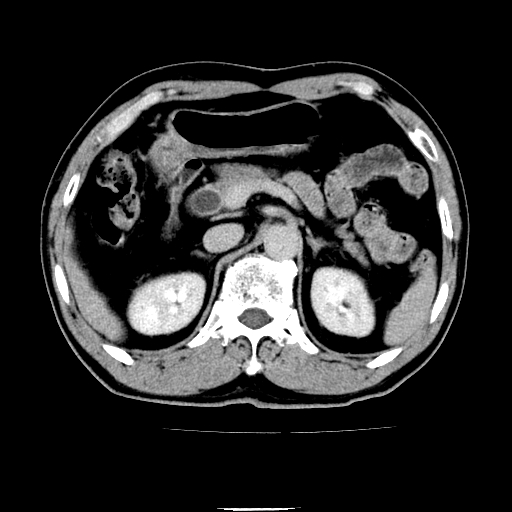

以下是引用chenqiong在2010-3-25 20:56:00的发言:[br]1、胆囊炎,胆囊息肉[br]2、肝内胆管及胆总管扩张,胆总管下端结石[br]3、十二指肠乳头旁憩室

以下是引用zxl51642在2010-3-26 10:47:00的发言:[br]胆囊炎,胆囊息肉,胆总管扩张,但未看到明显肿块,肝内胆管扩张不像恶性,炎性狭窄或阴性结石可能吧,建议mrcp,右肾小囊肿